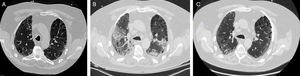

(A) Chest CT, performed 2 weeks before starting certolizumab pegol, showed centrilobular emphysematous changes in the upper lobes and subpleural reticular infiltrates. (B) Chest CT showed emphysema in the upper lobes, subpleural honeycombing, traction bronchiectasis bilateral peripheral ground glass opacities with an organizing pneumonia pattern. (C) A CT of the chest, performed three months after discharge, showed emphysema in the upper lobes and subpleural honeycombing, with resolution of superimposed ground-glass opacities and organizing pneumonia.

He presented to the emergency department with shortness of breath and cough. On early assessment, his heart rate was 112/min, his respiratory rate was 24/min, oxygenation saturation was 65% on room air, temperature was 98.6F, and normal blood pressure. Chest examination revealed more pronounced bilateral rales at the base. Initial laboratory data showed normal white cell count and serum electrolytes. His arterial blood gas showed a pH of 7.24, pCO2 of 69mmHg and po2 of 55mmHg on room air. The patient was intubated due to increased work of breathing upon admission. Blood, sputum and urine cultures were negative. Serum histoplasmosis antibodies, urine histoplasmosis antigen, serum coccidioidomycosis antibodies, and viral PCR panel were negative. Rheumatoid factor (RF) was 650IU/ml. Computed tomography (CT) of the chest showed emphysema in the upper lobes, subpleural honeycombing, traction bronchiectasis and superimposed bilateral peripheral ground glass opacities with an organizing pneumonia pattern (Fig. 1B). The patient was treated with vancomycin and cefepime. Bronchoscopy with bronchoalveolar lavage (BAL) showed predominant lymphocytes. The results of BAL studies, including bacterial, fungal, and acid-fast bacillus (AFB) culture and Mycobacterium tuberculosis (MTB) polymerase chain reaction (PCR) were negative. In the setting of persistent symptoms and a negative diagnostic workup, drug-induced interstitial pneumonitis was considered. We stopped certolizumab pegol as a therapeutic intervention because of a lack of improvement with appropriate antibiotics and negative cultures. He was treated with intravenous methylprednisolone 240mg/day for 3 days. He was extubated after 72h. He was weaned off oxygen before discharge. He was discharged on a tapering prednisone regimen over a 4-week period. A CT of the chest, performed three months after discharge, showed emphysema in the upper lobes and subpleural honeycombing, with resolution of superimposed ground-glass opacities and organizing pneumonia (Fig. 1C).